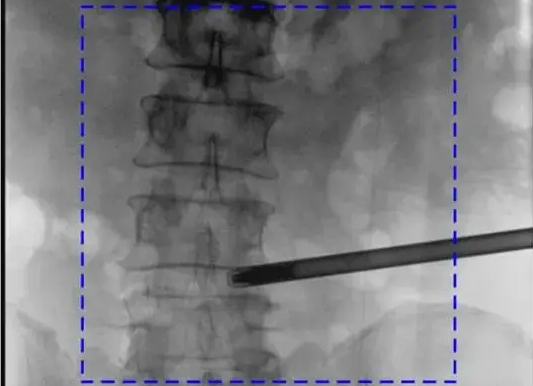

C臂機圖像不清楚的常見原因及解決辦法

C臂機作為骨科手術(shù)和介入治療的核心影像設(shè)備,其圖像質(zhì)量直接影響臨床診斷的準(zhǔn)確性。醫(yī)院在使用C臂機時,如果遇到圖像不清楚的情況,多半是有以下這些原因?qū)е碌?附解決辦法)。...